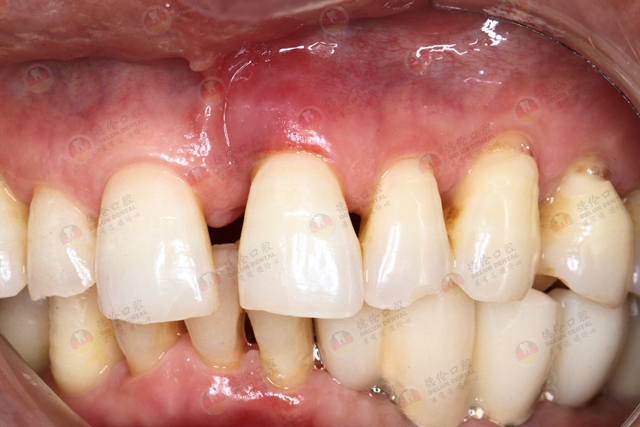

1、牙龈改变:正常牙龈粉红色、菲薄而紧贴牙面,附着龈有点彩。患牙龈炎时游离龈和龈乳头呈鲜红或暗红色,龈缘变厚,龈乳头圆钝,不再紧贴牙面;由于结缔组织内炎性浸润及胶原纤维消失,使原来致密坚韧的牙龈变得松软脆弱,缺乏弹性;同时由于牙龈肿胀或增生,龈沟深度增加,但上皮附着水平仍位于正常的釉牙骨质界,即出现假牙周袋。

6、龈和龈乳头变圆纯:龈炎主要表现为牙龈和龈乳头变圆纯,光亮,点彩消失,龈质粉软脆弱,缺乏弹性,龈探诊易出血,局部有牙垢或牙结石存在。